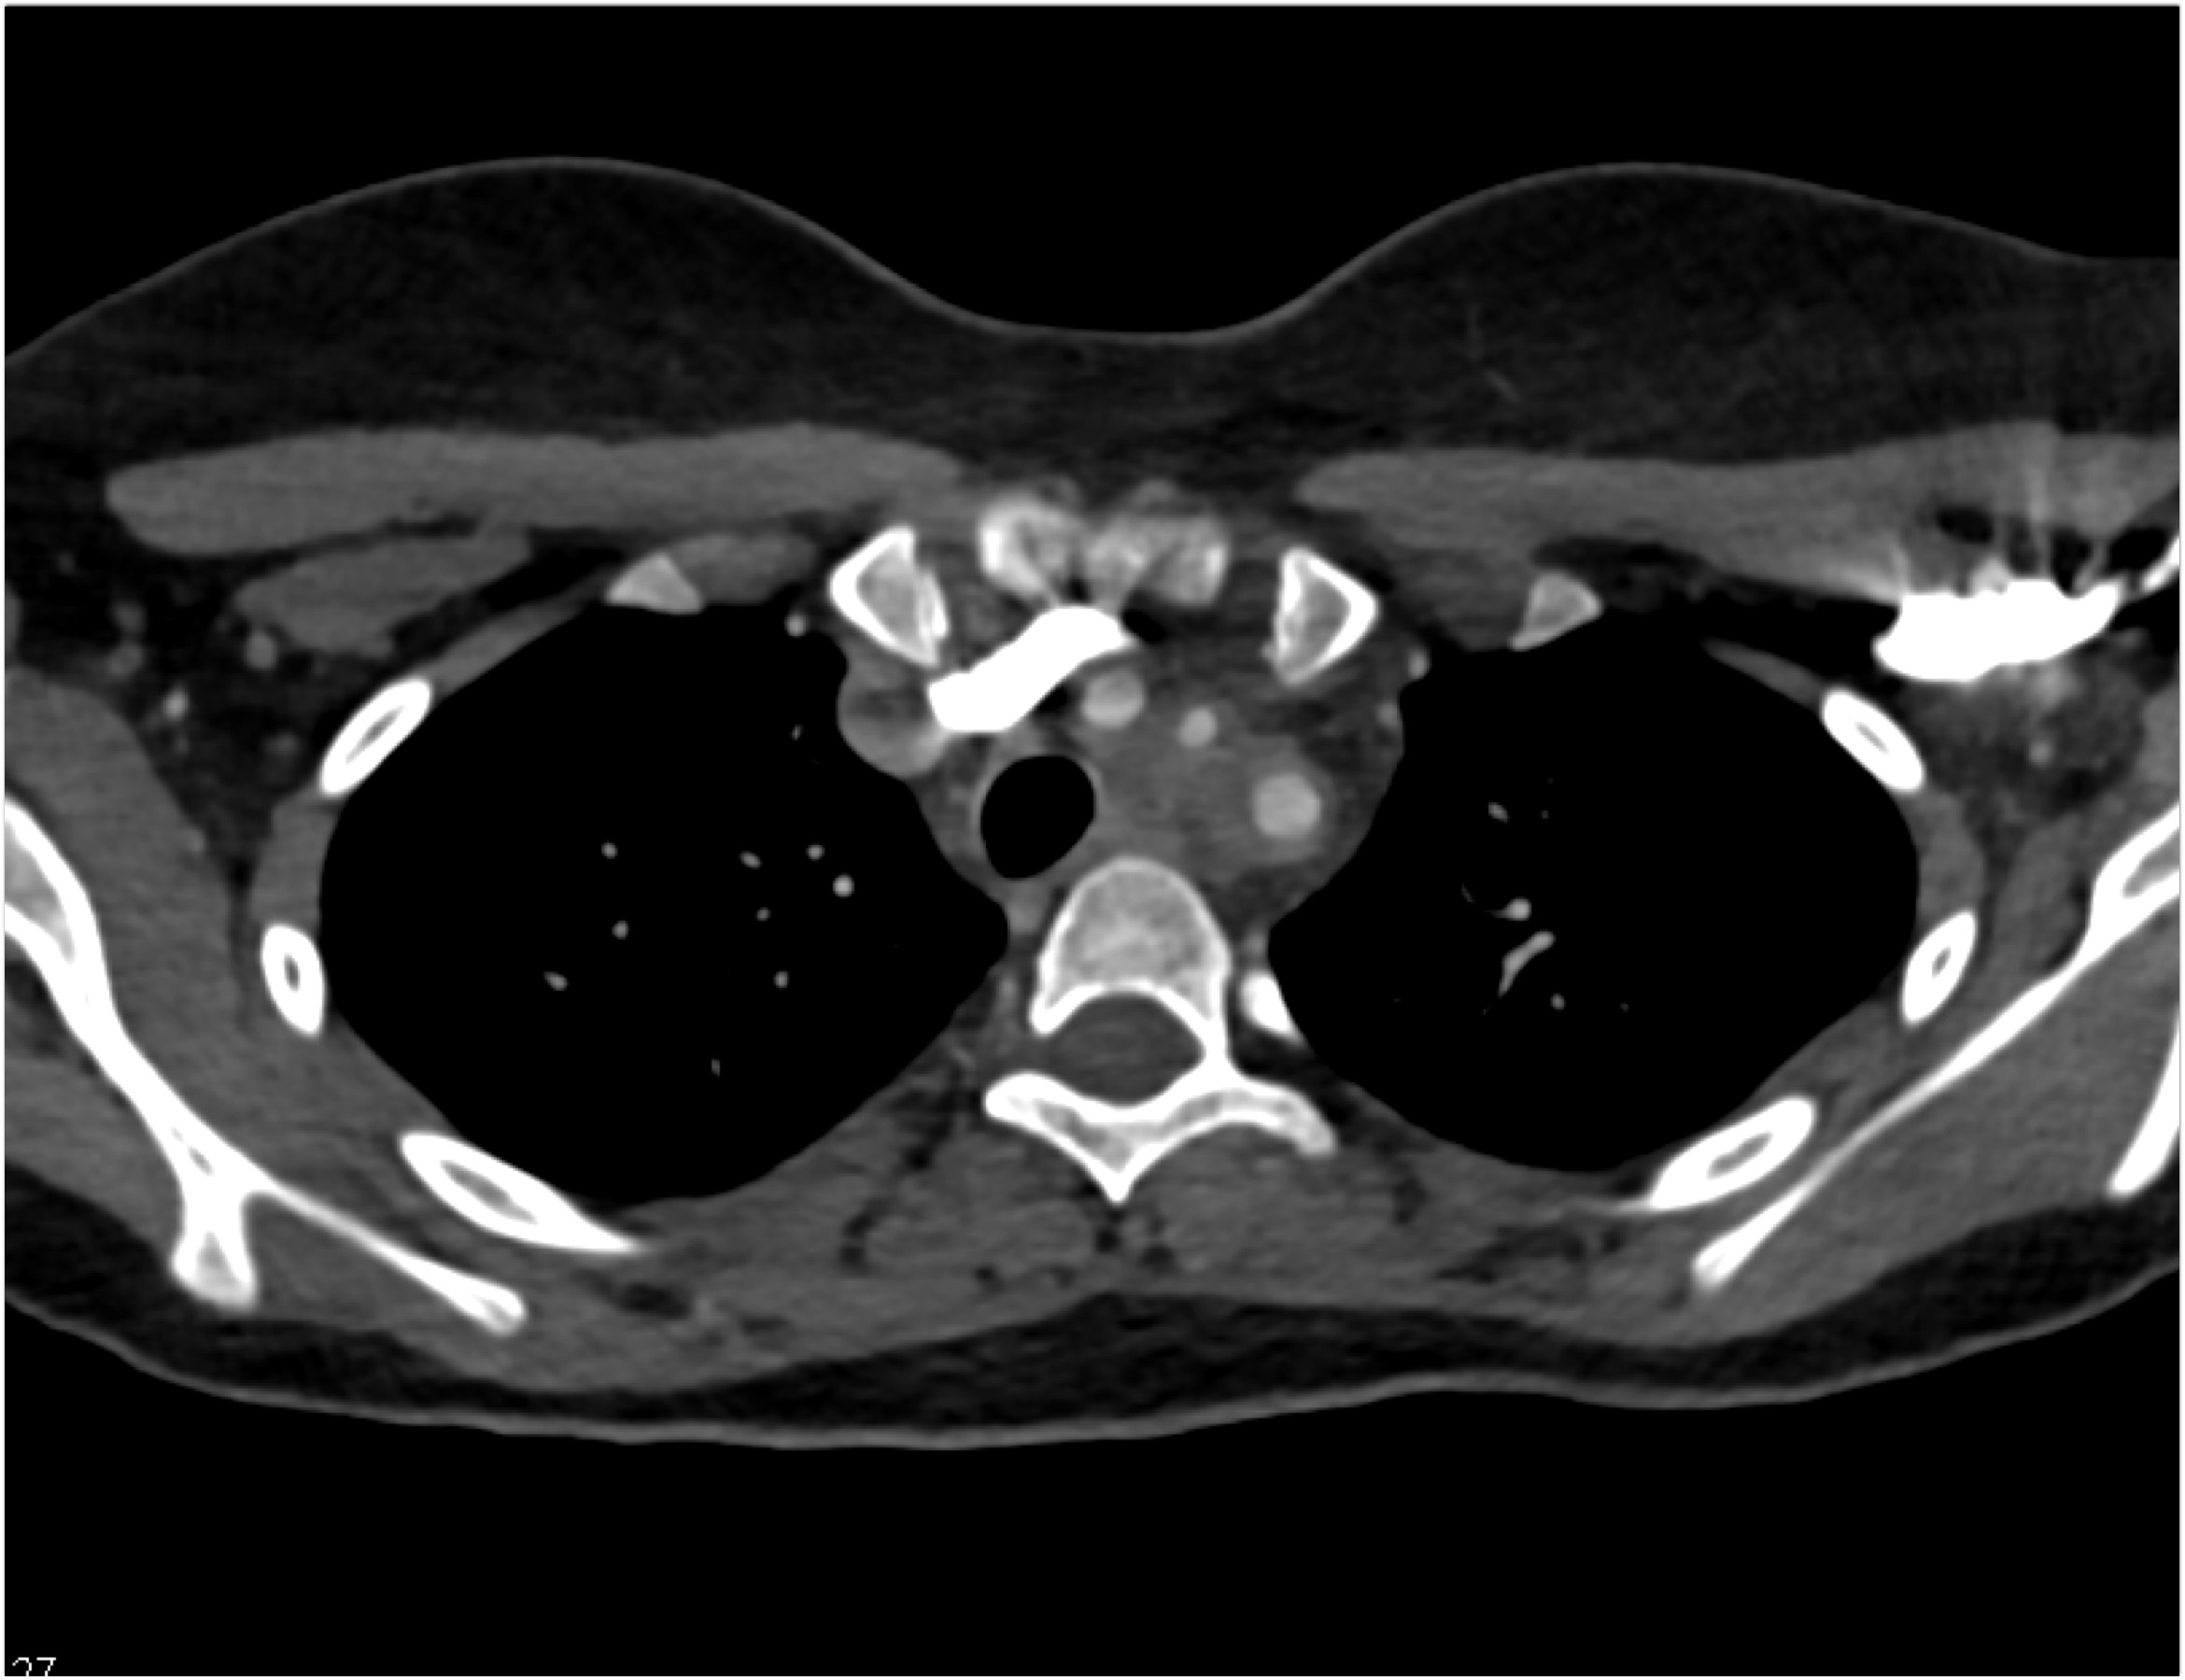

Diagnostic Case Quiz ❯ Anatomical Region Quiz: Chest

The most likely diagnosis in this case is?

Ehlers Danlos disease

Kawasaki disease

Takayasu’s aortitis

Ig4 vasculitis